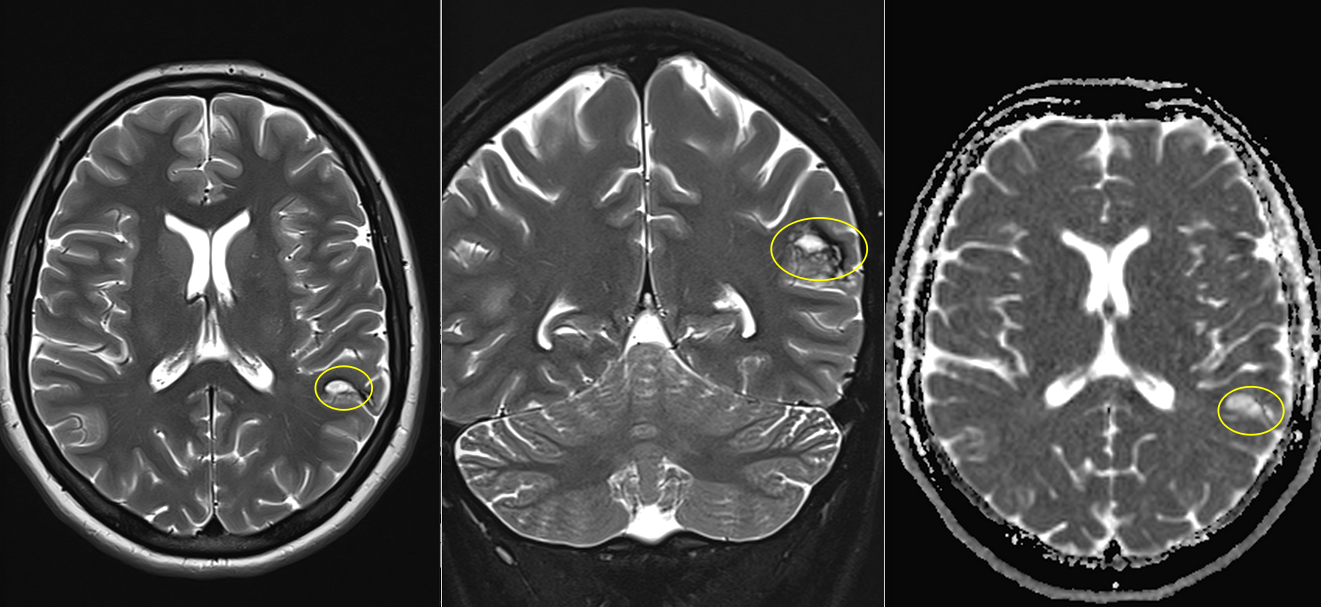

5. Tumora glioneuronală multinodulară și vacuolizantă (MVNT)

- Descoperită recent, frecvent diagnosticată prin RMN.

- Localizare: De obicei lob temporal.

- Aspect imagistic: Leziuni multinodulare neenhancement, bine delimitate.

- Clinic: Epilepsie.

- Tratament: Observație sau chirurgie dacă simptomatică.

- Grad OMS: 1

- Imagistică prin RMN: Aspecte caracteristice (leziuni corticale, fără edem semnificativ, fără contrast intens).